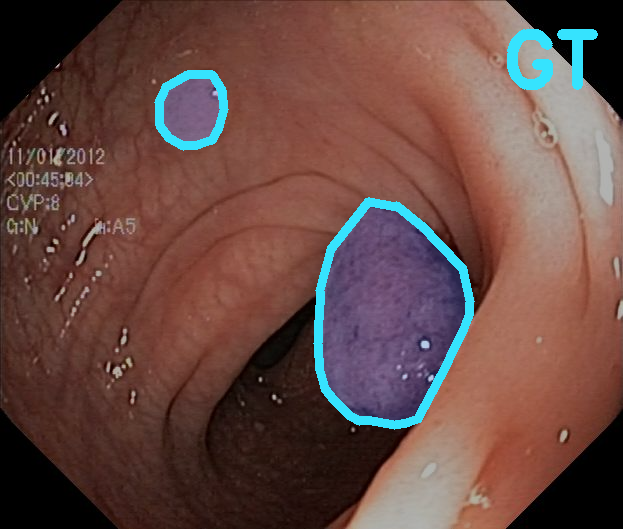

TransFuse is evaluated on both 2D and 3D datasets to demonstrate the effectiveness. As different medical image segmentation tasks serve different diagnosis or operative purposes, we follow the commonly used evaluation metrics for each of the segmentation tasks to quantitatively analyze the results. Selected visualization results of TransFuse-S are shown in Fig. 2.

Results of Polyp Segmentation. We first evaluate the performance of our proposed method on polyp segmentation against a variety of SOTA methods, in terms of mean Dice (mDice) and mean Intersection-Over-Union (mIoU). As in Tab. 3, our TransFuse-S/L outperform CNN-based SOTA methods by a large margin. Specifically, TransFuse-S achieves 5.2% average mDice improvement on the unseen datasets (ColonDB, EndoSene and ETIS). Comparing to other transformer-based methods, TransFuse-L* also shows superior learning ability on Kvasir and ClinicDB, observing an increase of 1.3% in mIoU compared to TransUnet. Besides, the efficiency in terms of the number of parameters as well as inference speed is evaluated on an RTX2080Ti with Xeon(R) Gold 5218 CPU. Comparing to prior CNN-based arts, TransFuse-S achieves the best performance while using only 26.3M parameters, about 20% reduction with respect to HarDNet-MSEG (33.3M) and PraNet (32.5M). Moreover, TransFuse-S is able to run at 98.7 FPS, much faster than HarDNet-MSEG (85.3 FPS) and PraNet (63.4 FPS), thanks to our proposed parallel-in-branch design. Similarly, TransFuse-L* not only achieves the best results compared to other Transformer-based methods, but also runs at 45.3 FPS, about 12% faster than TransUnet.